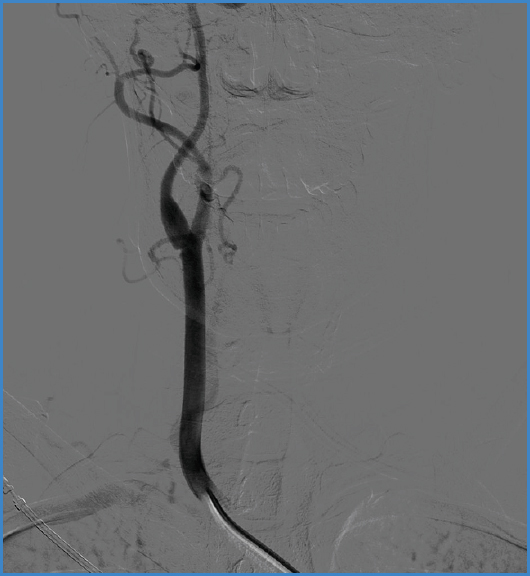

Mujer de 37 años sin antecedentes médico-quirúrgicos reseñables. Acude a urgencias por hemiplejia izquierda de 3 horas de evolución. Se diagnostica mediante tomografía computarizada (TC) cerebral de infarto de arteria cerebral media derecha, por lo que se realiza trombectomía mecánica urgente. Durante el procedimiento, se observa en la arteriografía septo no oclusivo en el segmento bulbar de la arteria carótida derecha, sugestivo de carotid web (Fig. 1). Descartado el origen cardíaco y como presentaba ritmo sinusal y ecocardiograma sin alteraciones, se solicita angiografía por TC, que confirmó dicho diagnóstico. Se decide endarterectomía de carótida interna derecha (Fig. 2) y cierre con parche de vena safena interna autóloga. Fue dada de alta después de 72 horas sin complicaciones. Posteriormente se observa permeabilidad a los 6 meses y ausencia de reestenosis.

Figura 1. Imagen de arteriografía tras el procedimiento de trombectomía urgente en la que se observa septo en carótida interna derecha sugestivo de carotid web.